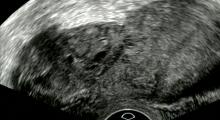

• Ultraschall der Blase